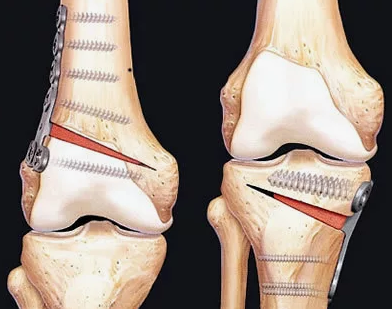

В случае перелома шейки бедра компания МосРентген Центр госпитализирует в Склиф для эндопротезирования.